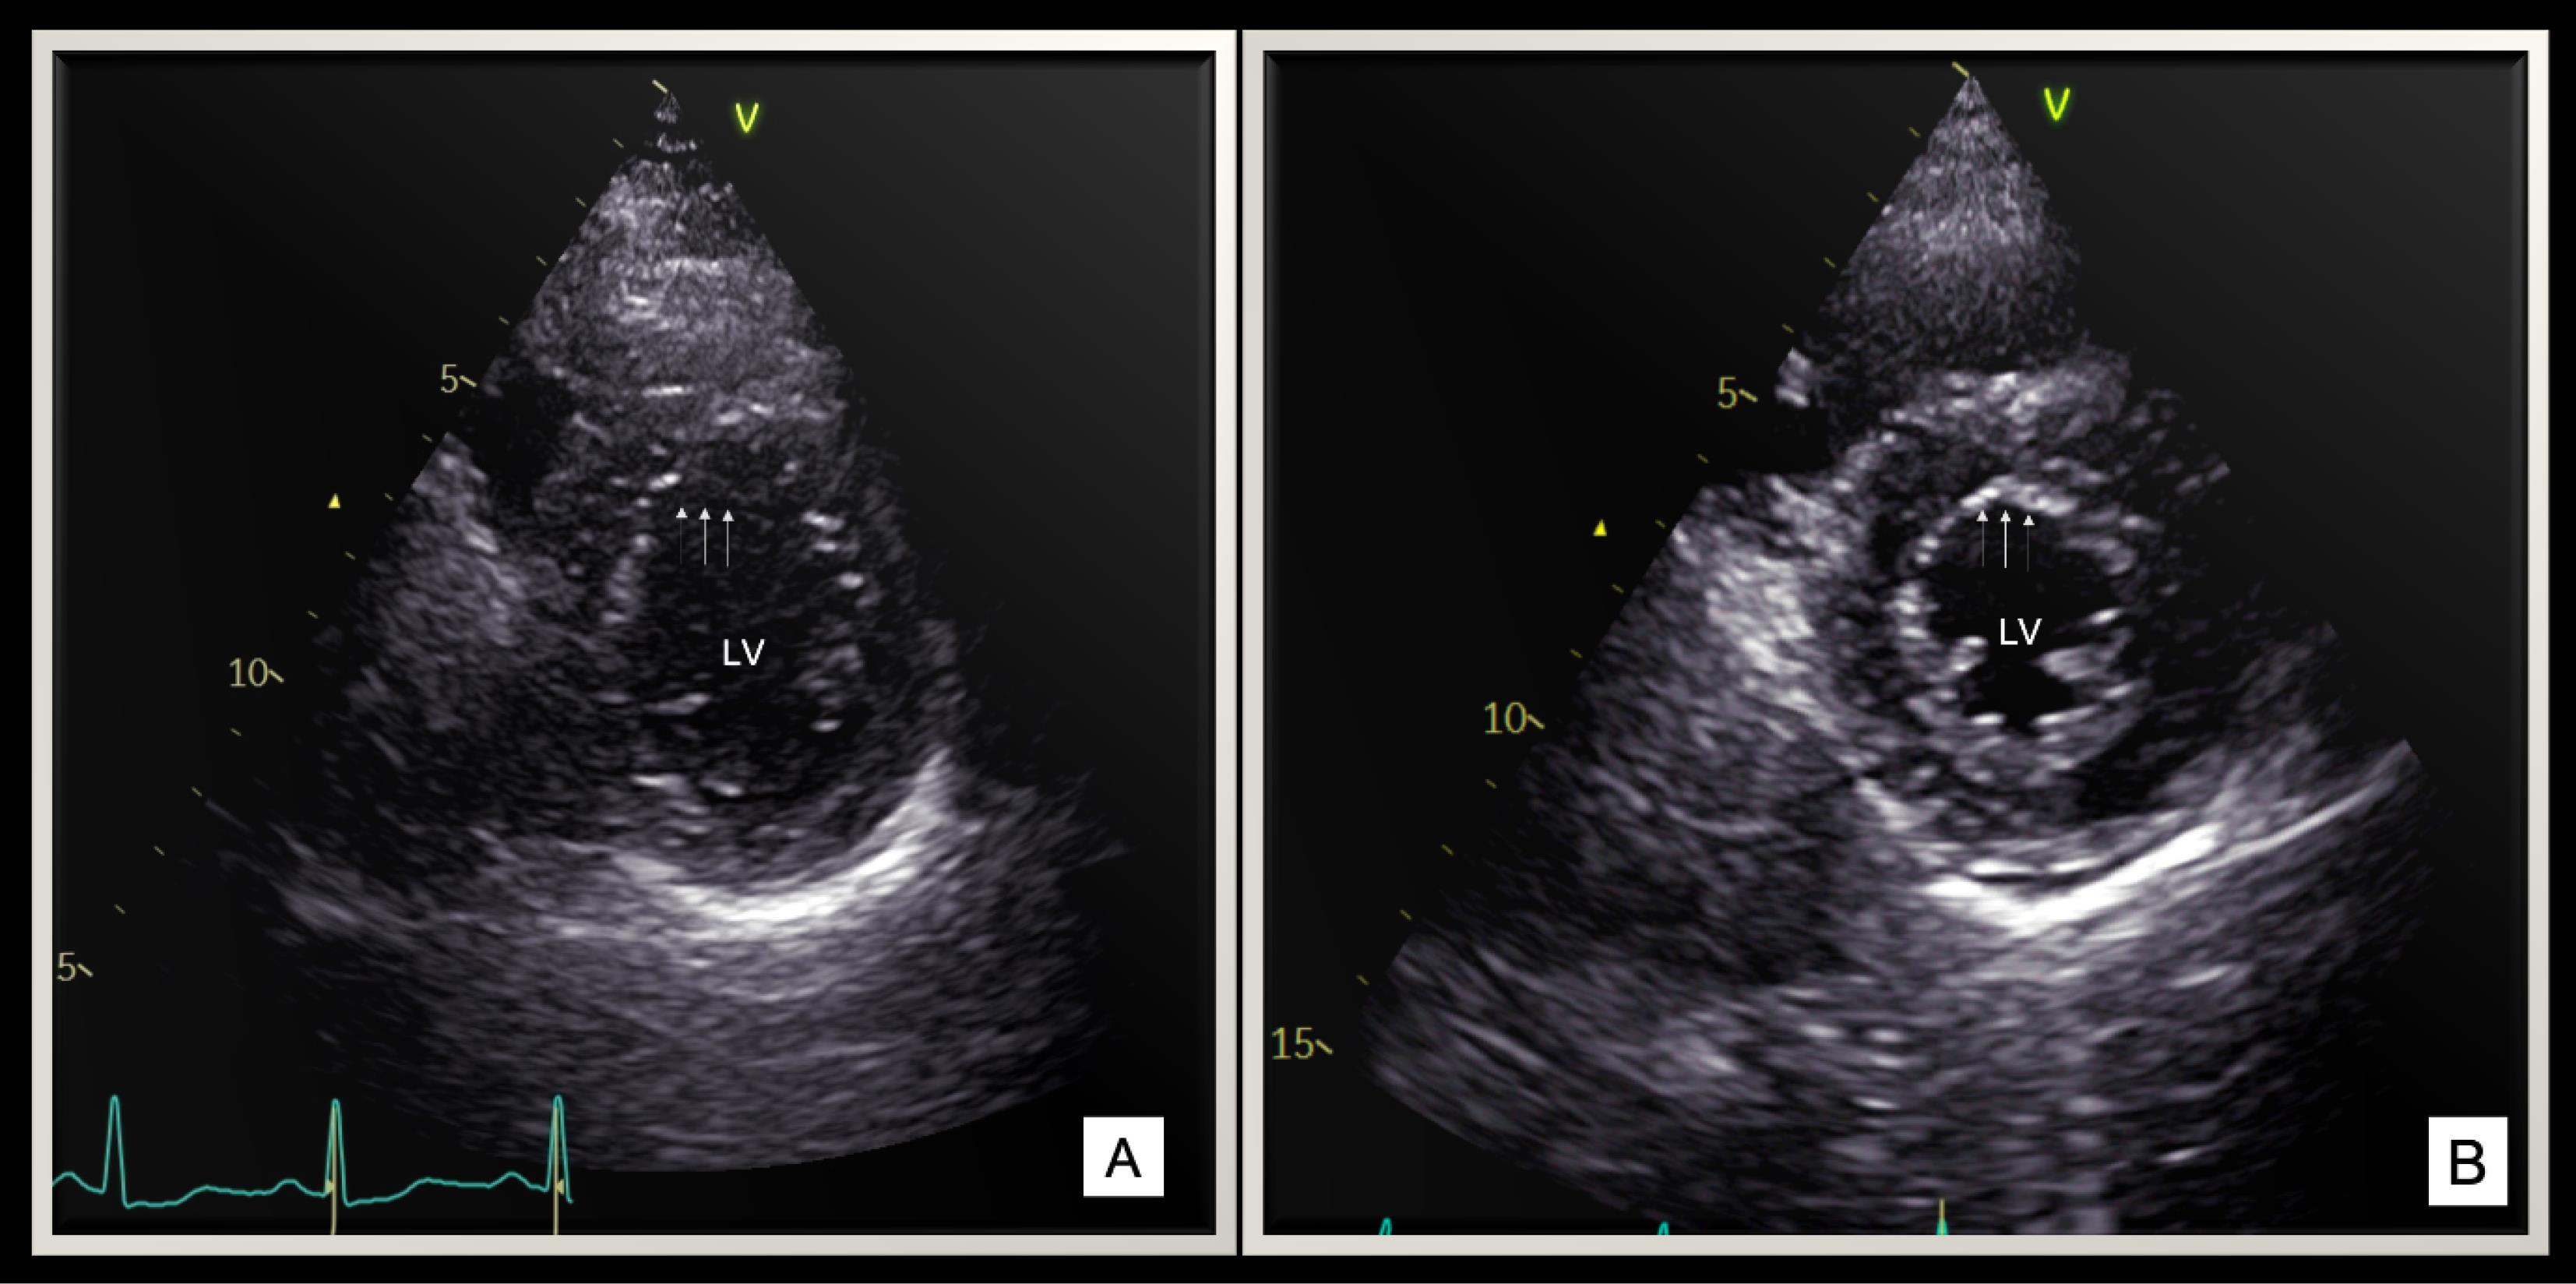

Echocardiography revealed normal sized left ventricle and preserved systolic function with a mean M-mode ejection fraction (EF) of 58.3 ± 6.7% in the study group. However, strain derived auto EF was significantly lower in 4 chamber (4C) as compared to 2 chamber(2C) (58.7 ± 4.7% vs 55.5 ± 4.1%, P = 0.002). This points towards the presence of regional myocardial dysfunction in these patients. All patients had myocardial involvement in the form of hypokinesia predominantly involving anterolateral, apicoseptal and apicolateral segments as compared to other segments (Figure 1 A, Table 2).

(A). Short axis view(SAX) at mid ventricular level showing hypokinesia of anterior and anterolateral segment (denoted by blue arrows). (B). The characteristic wall motion abnormality produces an appearance of an operculum resting on top of the heart

This characteristics wall motion abnormality produces an “operculum” like appearance over the other segments in the short axis view in systole (Figure 1B, Supplementary Video 1). Endothelial involvement was characterized by predominant involvement of interventricular septum (IVS) producing a characteristic jerky motion and stretching of IVS.

Supplementary video 1. Echocardiographic clip of short axis view at mid ventricular level shows hypokinesia of anterior and anterolateral segments, producing an operculum like appearance.

Rest all segments are contracting normally.